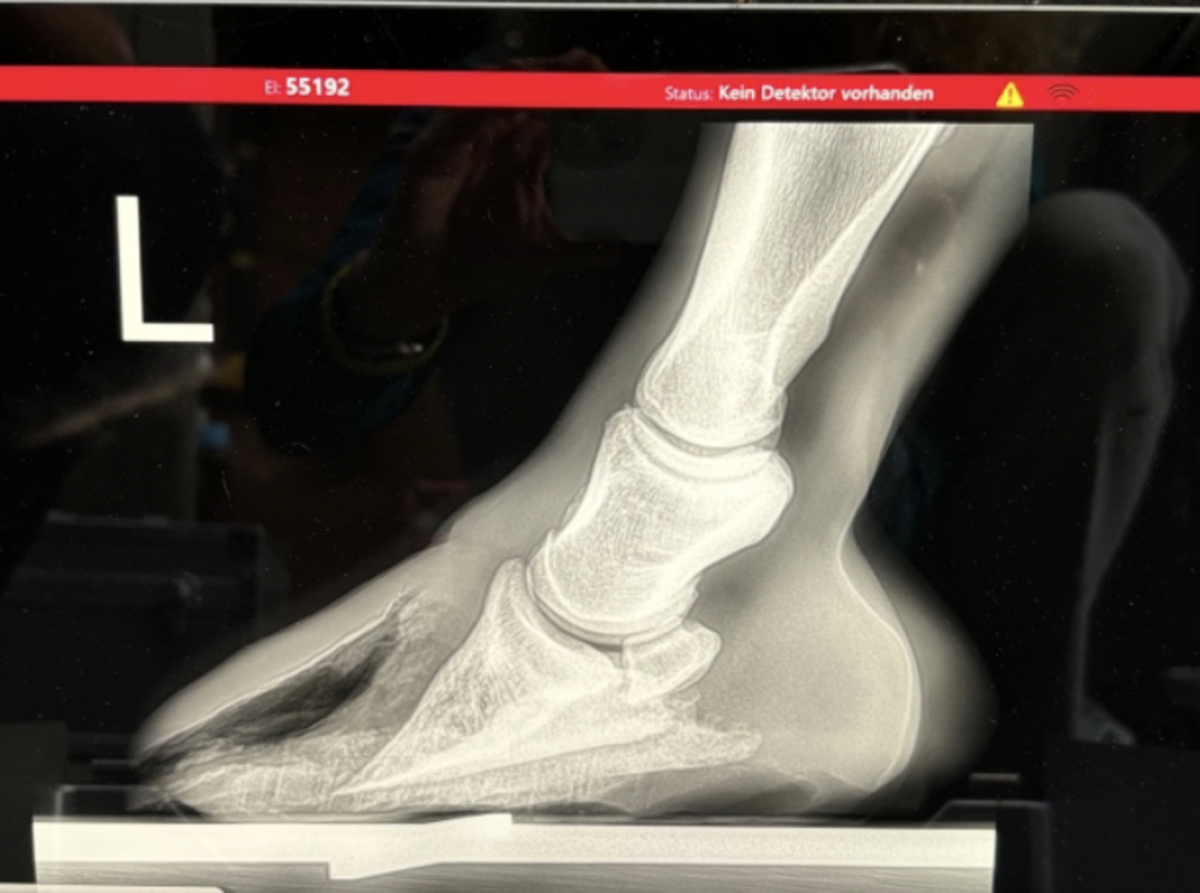

Vor über einem Jahr begann Mi Vidas Leidensgeschichte. Die Diagnose: White Line Disease, eine Hufkrankheit, die das Horn von innen zersetzt und äusserst langwierig zu behandeln ist. Für Mi Vida bedeutete das zahlreiche Tierarztbesuche, regelmässige Behandlungen und Spezialbeschläge alle vier bis sechs Wochen. In der Anfangszeit musste sein Huf sogar gegipst werden – heute gelingt es dank viel Geduld, Fachwissen und Kunsthorn, den Huf Stück für Stück wieder aufzubauen.